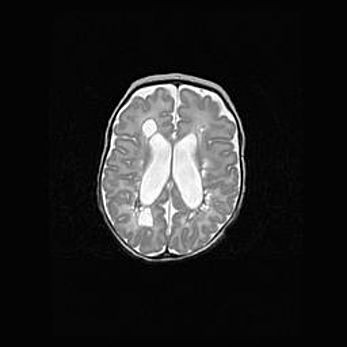

Лейкомаляция с кистозно-глиозной дегенерацией головного мозга.

Возраст: 2 месяца 25 дней

Вес: 6400 г

Окружность головы: 40 см

Срок гестации: 41 неделя

Лейкомаляцию относят к ишемически-гипоксическим повреждениям головного мозга, диагностируемым у новорожденных. При лейкомаляции в головном мозге обнаруживают очаги некроза, возникшие после тяжелой гипоксии и нарушения кровотока. В процессе морфогенеза очаги проходят три стадии: 1) развития некроза, 2) резорбции и 3) формирования глиозного рубца или кисты. Перивентрикулярная лейкомаляция (ПЛ) встречается примерно в 12% случаев среди новорожденных, обычно – у недоношенных детей, причем, частота ее зависит от массы, с которой младенец появился на свет. Наибольшее число малышей страдает лейкомаляцией, если масса при рождении 1500-2500 г.